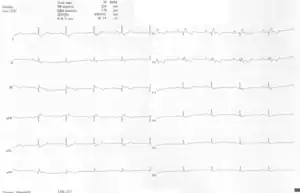

Other abnormalities that can be seen on the ECG include:

1. signs of right atrial enlargement or tall and broad 'Himalayan' P waves

2. first degree atrioventricular block manifesting as a prolonged PR-interval[5]

3. low amplitude QRS complexes in the right precordial leads

4. atypical right bundle branch block

5. T wave inversion in V1-V4 and Q waves in V1-V4 and II, III and aVF.[6]